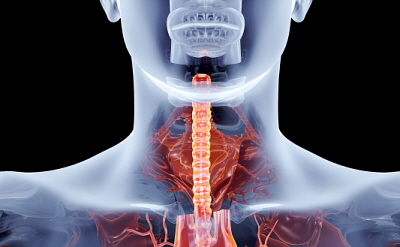

식도는 입과 위장을 연결하는 신체 장기의 일부입니다. 음식물을 섭취하면 식도를 통해 위장으로 전달됩니다. 식도의 이 부분에 암세포가 형성되면 이를 식도암이라고 합니다. 식도는 삼킨 음식물이 위장으로 내려가는 통로이며, 기도와 심장 뒤에 있는 약 35~40센티미터 길이의 관으로 소화 기능은 가지고 있지 않습니다.

일반적으로 식도암은 식도 점막층에서 거의 독점적으로 발생하지만, 의학적으로 식도암은 자궁경부 식도암, 흉부 식도암, 위식도 접합부암 등으로 세분화되며, 식도암 세포의 종류에 따라 편평세포암, 선암, 육종, 림프종, 흑색종 등으로도 나뉩니다.